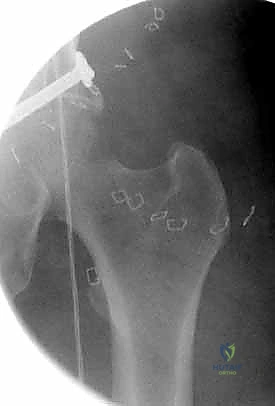

قبل بدء الجراحة، يتم رسم خطة دقيقة. يتم وضع المريض على طاولة العمليات المجهزة بأشعة (C-Arm) لضمان التصوير الفوري أثناء الجراحة.

المرحلة الثانية: الفتح الجراحي والوصول للعظم

يستخدم الدكتور هطيف تقنيات الفتح الجراحي المحدود (Minimally Invasive Plate Osteosynthesis - MIPO) كلما أمكن ذلك، للحفاظ على التروية الدموية للعظم وتسريع الالتئام. يتم عمل شق جانبي بعناية للوصول إلى منطقة الكسر دون الإضرار بالعضلات المحيطة.

المرحلة الثالثة: إرجاع العظم (Reduction)

هذه هي الخطوة الأكثر أهمية. يقوم الدكتور هطيف بإعادة القطع العظمية المكسورة إلى مكانها التشريحي الأصلي. إذا كان الكسر ممتداً داخل المفصل، يتم تثبيت السطح المفصلي أولاً باستخدام مسامير دقيقة لضمان سطح أملس يمنع الاحتكاك والخشونة مستقبلاً.